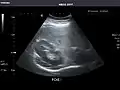

Abdominal Ultrasound (Full Exam)

STRUCTURED REPORT

(Technique: Transabdominal ultrasonography; Device: Toshiba Aplio XG)

Liver: Diffusely homogeneous and normal in echogenicity. No focal mass or contour nodularity. No intrahepatic biliary ductal dilatation.

Portal Vein: Patent main portal vein.

Gallbladder: No stones, wall thickening, or pericholecystic fluid.

Common Bile Duct: Nondilated measuring 1.3 mm at the level of the porta hepatis.

Pancreas: Visualized portions unremarkable.

Spleen: Normal in size.

Kidneys: Right and left kidneys measure 11.5 cm and 12 cm in length respectively. No hydronephrosis. Small left lower pole kidney cyst.

Ascites: None.

Aorta: Visualized portions normal in caliber, 16 x 15 mm.

IVC: Normal.

IMPRESSION:

Normal abdominal ultrasound.

Right kidney -